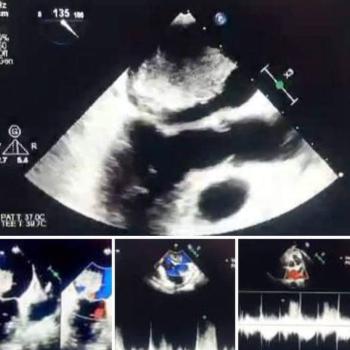

فريق طبي بمستشفى القلب بجامعة أسيوط ينجح في إنقاذ حياة مريضة تعاني من ورم بالقلب

كان مستشفى القلب بجامعة أسيوط استقبل مريضة من محافظة المنيا تبلغ من العمر ٥٦ عاما، تعاني من ضيق في…